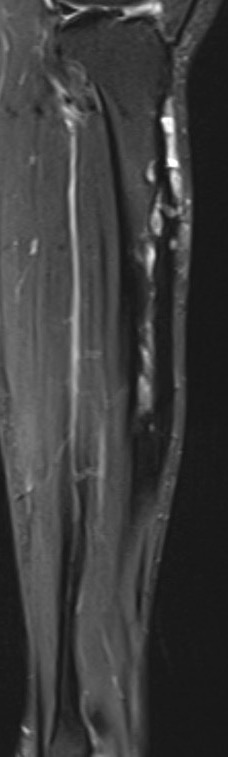

MRI

Khanna et al Skeletal Radiol 2008

- 24 cases of OFD / adamantinoma

- adamantinomas tend to be larger / cortical destruction / complete marrow involvement